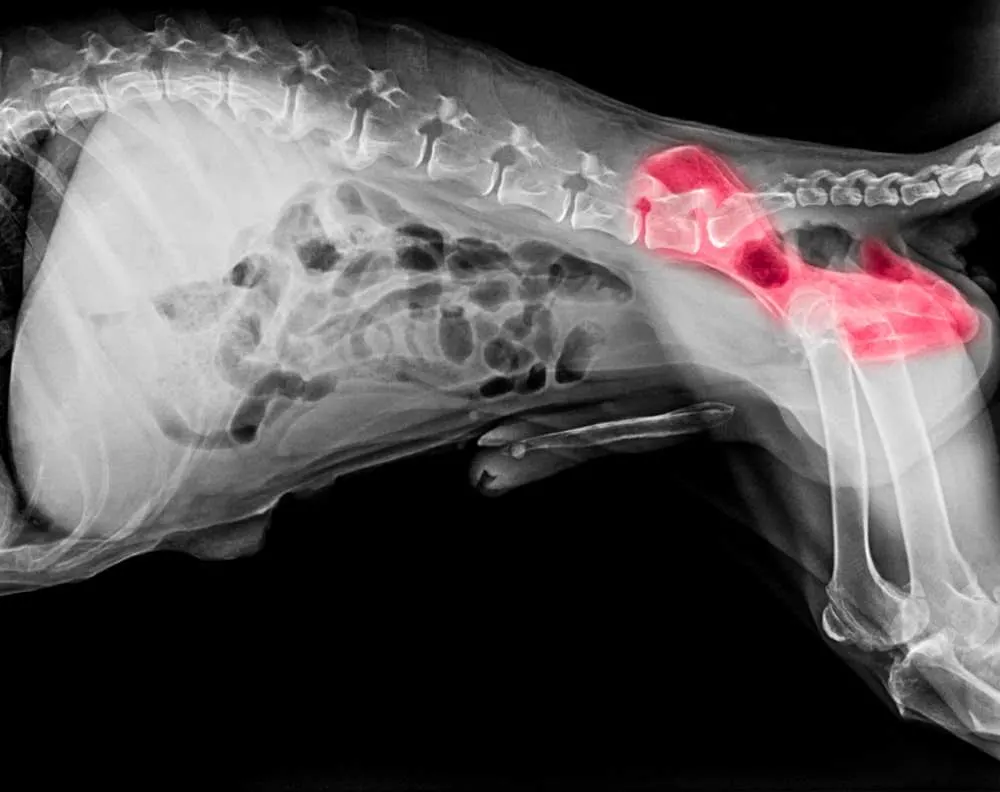

Hip Dysplasia

Hip dysplasia is maybe not the toughest disease on this list, but most certainly is one of the most common ones.

This disease is known to be a threat to many dog breeds, including corgis. There’s not much variations in hip dysplasia when talking about other breeds, it almost always manifests itself in similar form with similar symptoms.

This disease affects development of the hip joint, thus causing loss of function of the said joint. This does not happen overnight, but slowly which means it can be detected in time.

Early detection means that you can prevent it from getting worse for some time, but you can’t stop the dysplasia without a surgical intervention.

If this is handled in time, your dog can make a full recovery depending on the age and a state of your dogs health.

Some puppies as young as five months can exhibit some hip dysplasia symptoms, which means their hip joints aren’t in the best condition. Remember, this is not an old dogs disease and can affect any breed at any time.

A surgical procedure that is performed on a dog with hip dysplasia is a relatively common one, and it doesn’t bring a lot of risk with it.

Depending on the state of disease the cost for this operation can be between $1000 and $6000. The earlier you notice the symptoms, less complicated and less pricey the surgery.

Some of the most common symptoms of hip dysplasia are:

- Loss of joint function (this can be more or less noticeable depending on the stage of the disease)

- Limping (this occurs when hip dysplasia takes its toll)

- Space between legs may appear wider than usual

- The leg may be rotated outward

If you see any of these symptoms you should immediately take your corgi to the vet.

One more thing that can help are regular checkups at the vet, because they can see signs of hip dysplasia much easier than you.

There are also anti-inflammatory medication treatments that can help your corgi when dealing with hip dysplasia.